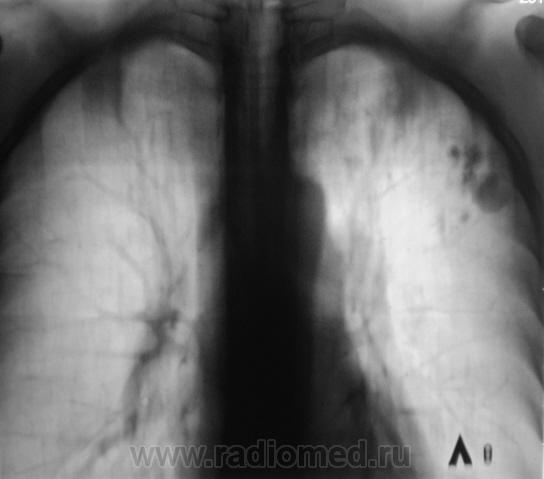

Пациент прооперирован - лобъектомия.

После операции.